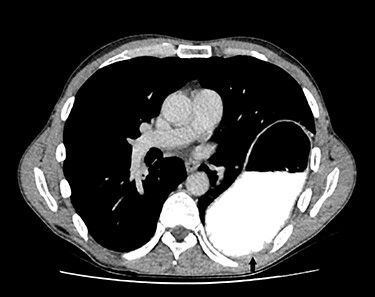

For primary diagnosis, computed tomography (CT) scan is most accurate when suspecting a diaphragmatic lesion [1]. Lesions without herniation are difficult to detect even in thin slices with multiplanar reconstruction. Possible direct signs, besides discontinuity, are the ‘dangling diaphragm sign’, showing a rolled up free diaphragmatic border. Indirect signs are the ‘collar sign’, organs are constricted when passing through the defect (Fig. 1), or the ‘dependent viscera sign’, where abdominal organs touch directly the thoracal wall without interposition of the lung in the supine patient [1, 3] (Fig. 2).

A 47-year-old male patient consulted our emergency department with acute epigastric pain without dyspnea or alteration of bowel function. A thoracic X-ray showed a dilated stomach intrathoracally and colon parts. A CT scan confirmed a left-sided diaphragmatic hernia (69 × 45 mm) with an upside down stomach, herniating small bowel and colon (Figs 1 and 2). The patients’ history includes a severe motor vehicle accident 20 years ago with following coma during 3 months but without abdominal surgery, suggesting a traumatic origin of the hernia.